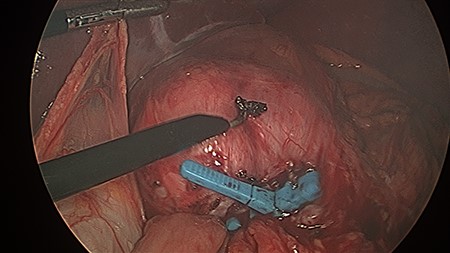

The patient was positioned supine, and cut down entry periumbilically was performed with a 10-mm camera port and two 5-mm working ports inserted. On laparoscopy, a retrograde intussusception with the intussuscipien constituted the gastric pouch and the intussusceptum constituting the alimentary limb of the jejunum was identified. Just distal to the intussusceptum, there was a jejunal mesenteric defect, with demonstrable thinning of mesenteric fat and various tears. Through this defect, the remnant stomach, normally situated on the left side of the gastric pouch, was found to have herniated from the left to right through this jejunal mesenteric defect, posterior to the alimentary limb in the supracolic compartment. This internal hernia was reversed and the defect closed with non-dissolvable V-Loc™ barbed sutures. A slipped MiniMizer gastric ring was then identified 3 cm distal to the gastrojejunal anastomosis (Fig. 2). No fixation sutures were identified. On release of the ring, 25 cm of alimentary limb jejunum was, with gentle traction, pulled from its invagination into the gastric pouch through where the ring was originally placed (Fig. 3). Surprisingly, all bowel was viable and no resection was required.

This figure demonstrates operative findings prior to surgical manipulation. The MiniMizer band is present at forefront, 3 cm distal to gastrojejunal anastomosis. The intussusception and internal herniation may be difficult to appreciate from this image.